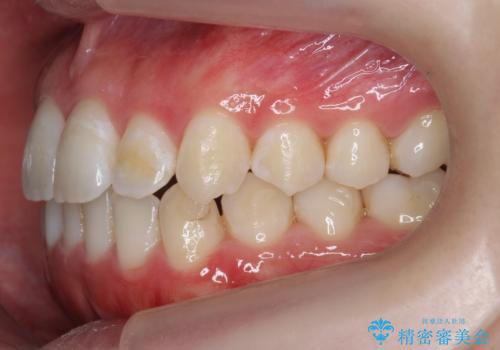

下の歯のがたつき 上より気になる

- 前歯のがたつきが気になって来院。

下の歯のがたつきが上よりも多い状態でした。

下の前歯は上の歯の内側にあるため、外に並べることができないため、上ほど簡単ではありません。

すき間をしっかりとって並べる必要があります。

今回は、下の歯を健康に支障が出ない範囲でわずかに削合し、並べるようにしました。(ディスキングといいます)

前歯のがたつきもしっかり治り、喜んでいただけました。

下の親知らずは虫歯になっていたため矯正前に抜歯しています。